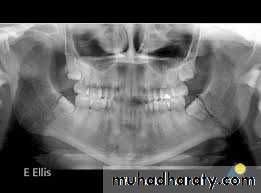

2. Extra-oral radiographsI. Oblique lateral of mandible (right and left side views); to evaluate thefracture line in the body, angle and condylar neck fracture.II. Postero-anterior view of mandible; to evaluate body and angle #together with the type of displacement.III. Panoramic tomogram, or orthopantomogram (OPT): the best single overallview of the mandible, including excellent view of the condyles.tic resonance imaging); which gives very accurate details.

IV. Reverse Towne's view (elongated PA); to demonstrate fractures of thecondylar neck.v. Temporomandibular joint views (in open and close mouth); todemonstrate the presence of TM dislocation (Transcranial,Transpharyngeal, Arthrography, and Arthroscopy)VI. CT scan (computerized tomography scanning); to evaluate intracapsular fracture of the condylar head.VII. MRI